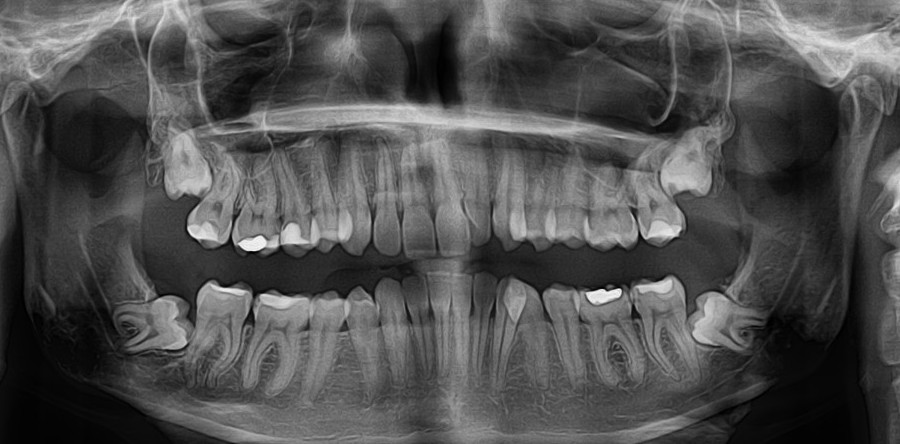

Obecnie dzięki bardzo prężnemu rozwojowi technologii możemy skorzystać z niezwykle dokładnego badania tomografem. Komputerowe tomografy stożkowe pokazują obraz 3D. W trakcie tylko jednego obrotu lampy wykonywanych jest od 300 do 600 zdjęć. Trójwymiarowy obraz jest przetwarzany na bardzo wiele sposobów. Wszystko to ma na celu jeszcze lepsze zaprezentowanie badanych struktur wewnętrznych i ułatwienie leczenia nieprawidłowości. Tomografia komputerowa zębów umożliwia wykrycie m.in. próchnicy jeszcze na bardzo wczesnym jej etapie. Na obrazie widoczne są również torbiele i zmiany nowotworowe. Tomografia komputerowa wykaże również obniżenie brzegu kostnego, ubytki kostne, rozrosty nienowotworowe, a także zęby zatrzymane. Tomografia komputerowa znalazła swoje zastosowanie również w ortodoncji. Dzięki niej można łatwo oszacować, ile jest zawiązków zębów w okresie rozwojowym małego pacjenta. To w znaczącym stopniu pomaga w dobrym zaplanowaniu leczenia.